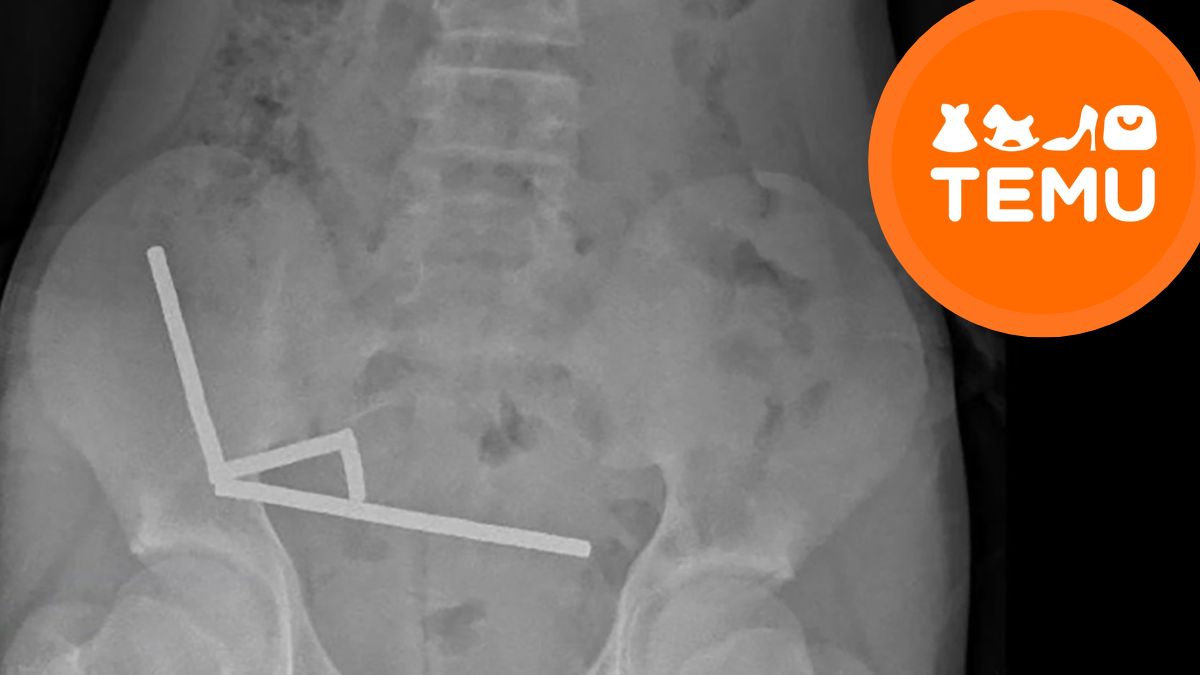

The issue isn’t just that he swallowed them; kids do dumb things, to be fair, but what happens after they’re ingested. These aren’t your typical fridge magnets; we’re talking about neodymium magnets, which are top-tier in terms of magnetic force, even at their tiny 5x2mm size. An X-ray of the boy’s abdomen showed that all those magnets had clumped together into four straight lines inside his intestines.

It looks like they were trying to find each other, with the doctors noting that “These appeared to be in separate parts of bowel adhered together due to magnetic forces.” You’re probably picturing a single chain of magnets, but the terrifying reality is that magnetic forces pulled four separate parts of his bowel together. This created incredible pressure, causing what doctors call “necrosis,” tissue death, in four different spots of his small bowel and caecum, which is part of the large intestine.